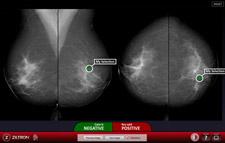

One of Ziltron’s early customers is BreastScreen Australia (BSA), which aims to reduce morbidity and mortality from breast cancer in Australia by the early detection of breast cancer. The BreastScreen Reader Assessment Strategy (BREAST) is a resource by which BreastScreen Australia may continue to meet these aims.

The strategy is based on digital screen reading test sets by Ziltron designed to assess performance of screen readers and provide immediate feedback to individual readers and BreastScreen Services.

· Diagnostic assessment: The company’s digital imaging diagnostics suite allows users to diagnose confirmed cases; the technology then measures the ability of the user to make a correct diagnosis, and compare that diagnosis to the universe of others who have taken the same test.